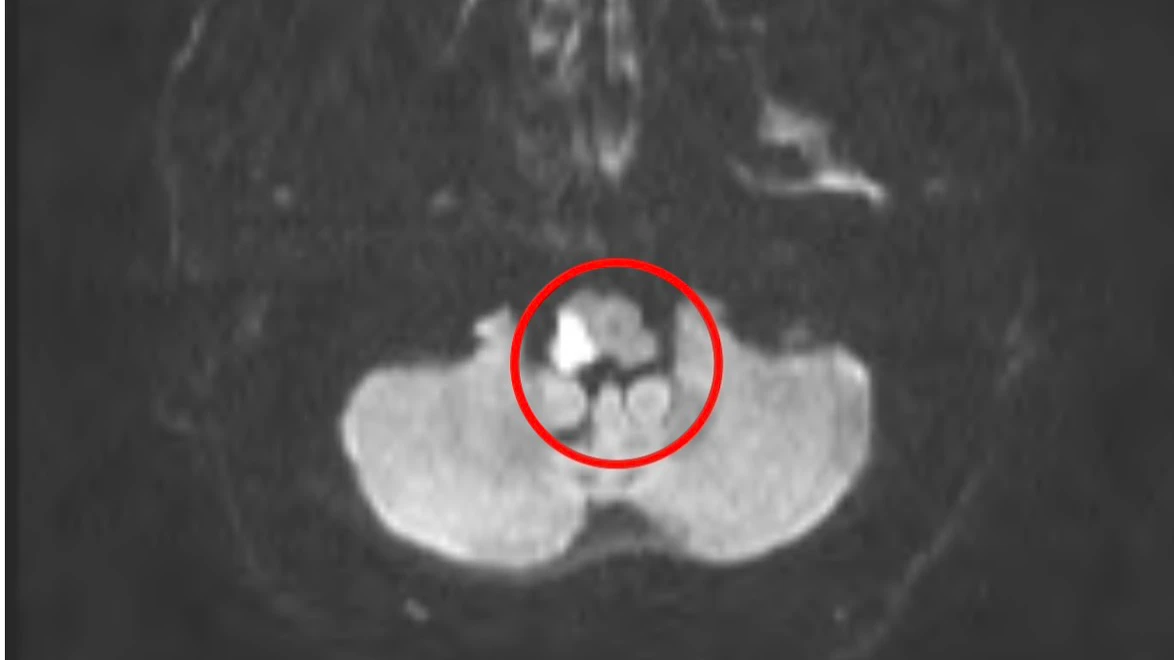

吳宇軒指出,許男送醫時並未出現「臉歪、手腳無力、口齒不清」等典型中風症狀,僅有走路不穩,經神經理學評估雖無偏癱、複視,但小腦測試呈現右側距離判斷不良,醫療團隊高度懷疑為小腦或腦幹中風,透過核磁共振確認「腦幹右側、延腦外側」出現明顯梗塞。